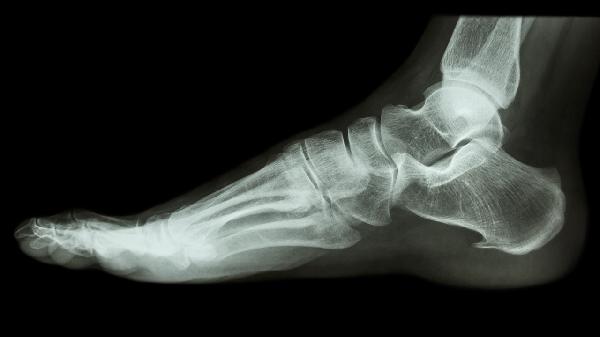

跟骨骨折术后住院时间主要取决于手术创伤程度和个体恢复差异。采用微创内固定术的患者,若术后伤口无感染、疼痛控制良好且能借助助行器短距离移动,通常5-7天可达到出院标准。开放性复位或合并软组织损伤的患者,需观察伤口愈合情况并预防感染,住院时间可能延长至7-10天。术后早期需通过X线确认骨折复位稳定性,配合康复指导训练踝关节活动度。出院前需确保患者掌握伤口护理方法,并能正确使用拐杖或支具避免患肢负重。